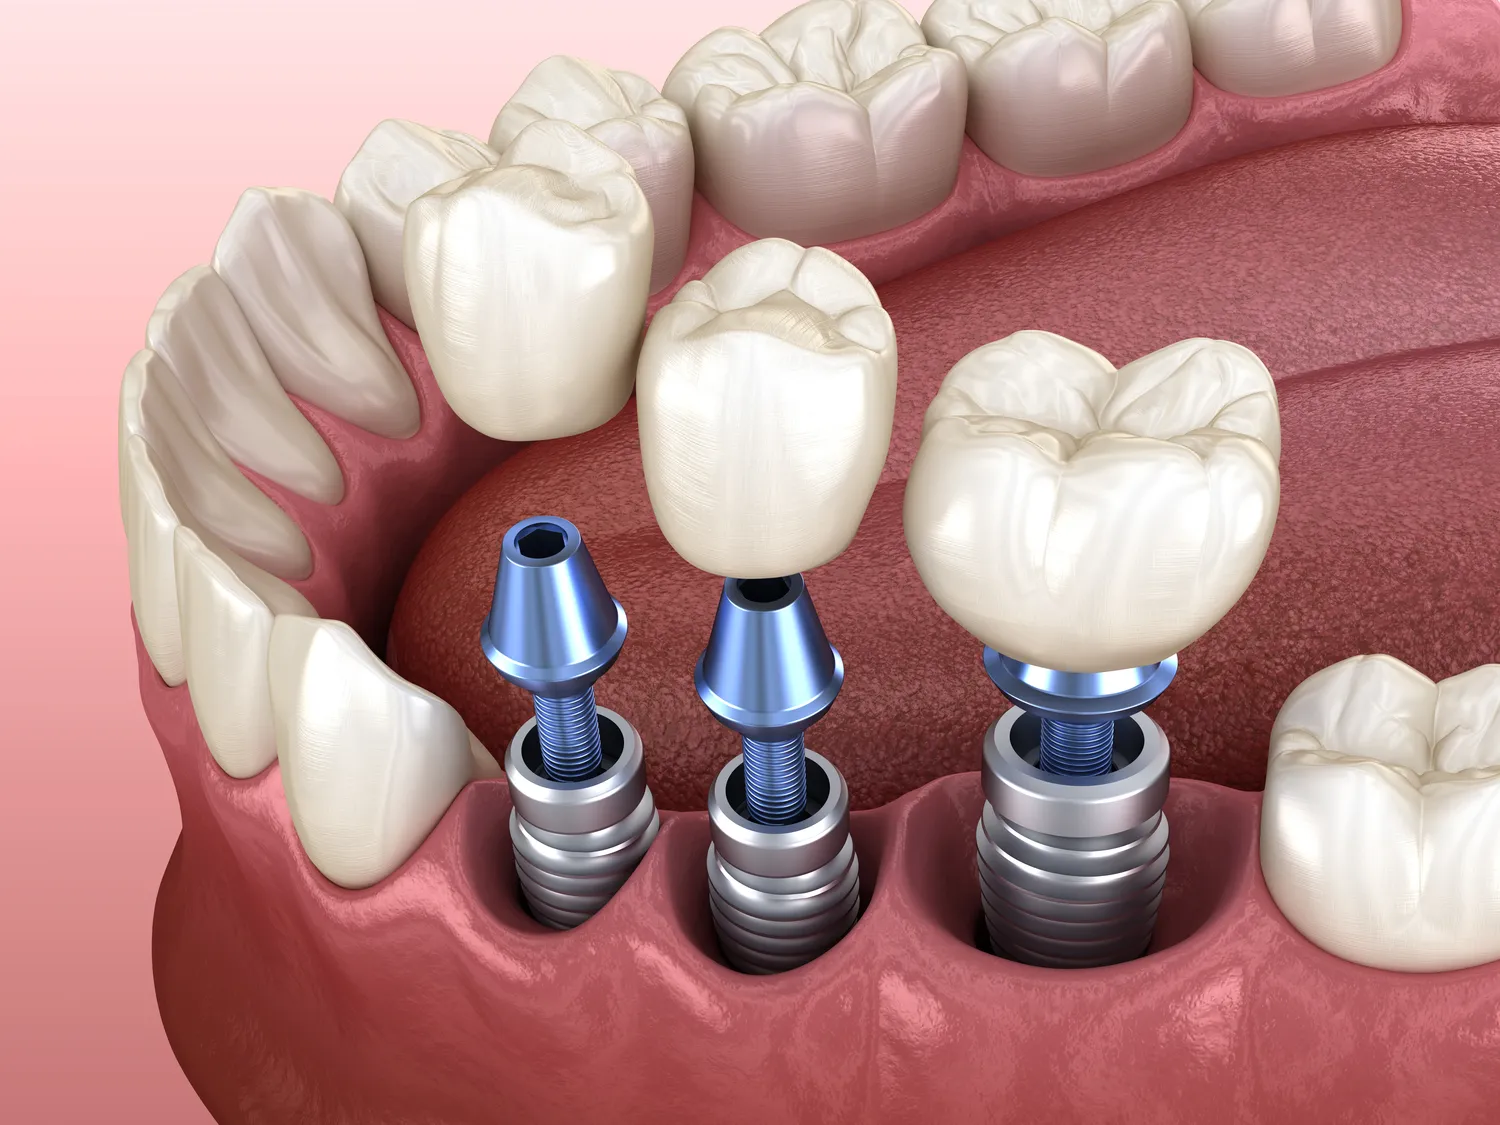

Proces wszczepienia implantu zębowego składa się z kilku etapów, które są kluczowe dla osiągnięcia sukcesu całej procedury. Pierwszym krokiem jest konsultacja stomatologiczna, podczas której lekarz ocenia stan zdrowia pacjenta oraz wykonuje zdjęcia rentgenowskie lub tomografię komputerową w celu oceny struktury kości. Na podstawie tych informacji lekarz podejmuje decyzję o dalszym postępowaniu oraz planuje szczegóły zabiegu. Następnie następuje właściwe wszczepienie implantu; podczas tego etapu chirurg wykonuje nacięcie w dziąśle i umieszcza tytanowy implant w kości szczęki lub żuchwy. Po zakończeniu tego etapu następuje okres gojenia, który może trwać od kilku tygodni do kilku miesięcy. W tym czasie implant integruje się z kością, co jest kluczowe dla jego stabilności i funkcjonalności. Po zakończeniu procesu gojenia następuje kolejny etap – zakładanie korony protetycznej na wcześniej wszczepiony implant. Korona jest dostosowywana do kształtu i koloru naturalnych zębów pacjenta, co zapewnia estetyczny efekt końcowy.